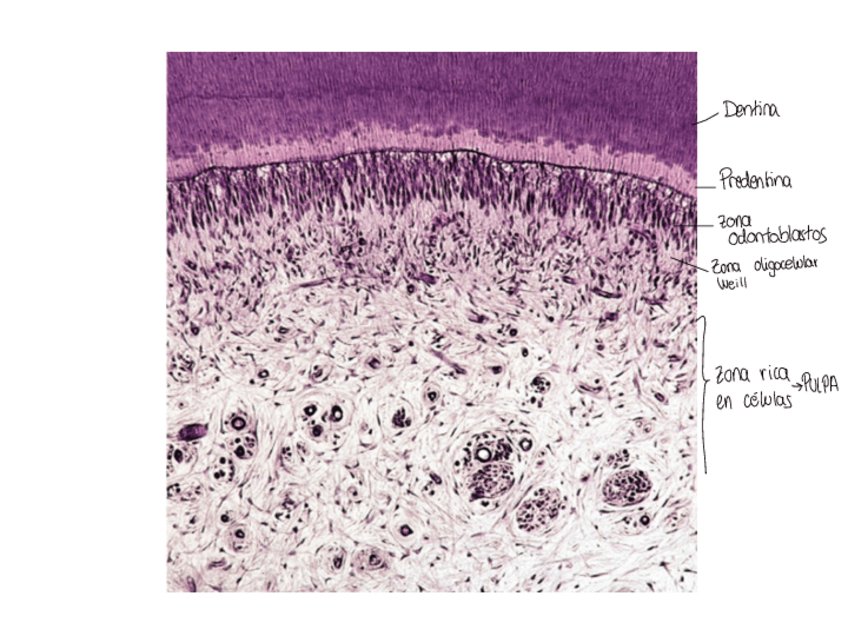

Imágenes de examen